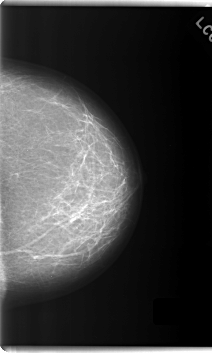

C_0209_1.LEFT_MLO

C_0209_1.LEFT_CC